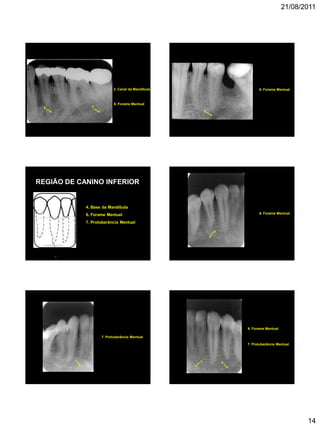

14

6

2. Canal da Mandíbula

2

6. Forame Mentual

REGIÃO DE CANINO INFERIOR

4. Base da Mandíbula

7. Protuberância Mentual

7